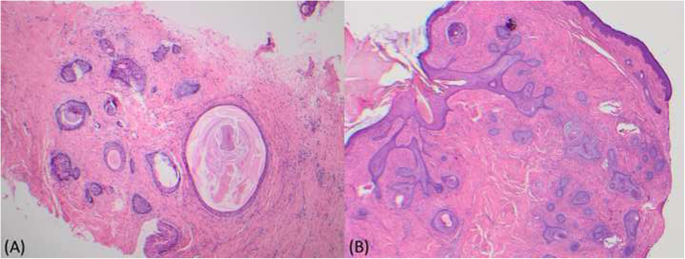

A total of 15 publications reporting 19 individual case reports of eyelid trichofolliculoma were identified, including one case at our institution in the present publication. This was a 75-year-old man presented with a 10-year history of an exophytic nodule of the left upper eyelid with associated visual obstruction (Fig. 1). An initial snip biopsy demonstrated a large, dilated, and plugged central hair follicle from which many secondary follicles radiated into the surrounding densely fibrotic stroma. The patient proceeded to surgical extirpation by a plastic surgeon. The dermis was expanded by tumoral process composed of multiple varying sized hair follicles in a cellular fibrous stroma. Dilated infundibula were noted with foci of calcification visualized within the lesion and the surrounding dermis and within the lesions. The pathology was consistent with trichofolliculoma (Fig. 2).

a Initial snip biopsy demonstrated a large, dilated, and plugged central hair follicle from which many secondary follicles radiated into the surrounding densely fibrotic stroma. b Excisional biopsy histopathology demonstrating a large, dilated, and plugged central hair follicle from which many secondary follicles radiated into the surrounding fibrotic stroma, consistent with trichofolliculoma